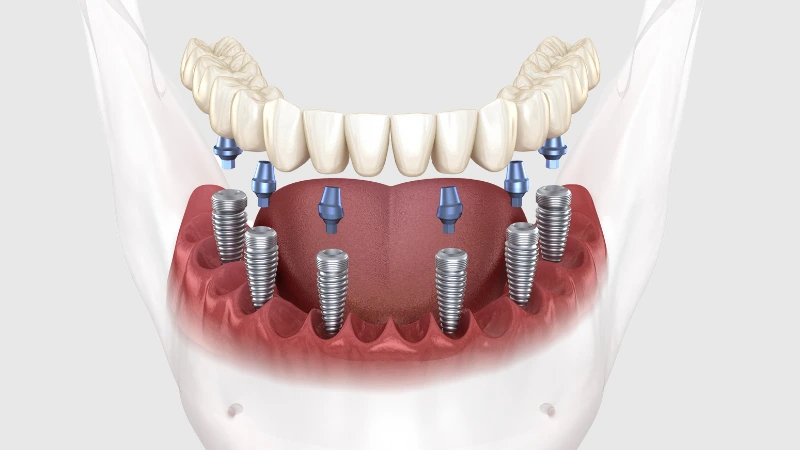

All on Four ve All on Six İmplant

Tamamen dişsiz veya kalan dişleri çekilmesi gereken hastalar için tek bir operasyonda ve tek bir protez ile sabit dişlere kavuşma imkanı sunan yenilikçi çözümlerdir. Hızlı iyileşme ve yüksek konfor sunar.

3) All-on-Four / All-on-Six bana uygun mu?

Tam dişsizlikte tek aşamada sabit proteze geçiş için iyi seçeneklerdir. Kemik hacmi, sistemik durum, sigara alışkanlığı ve hijyen motivasyonu değerlendirilir. Geçici–kalıcı protez zamanlaması hastaya özelleştirilir.